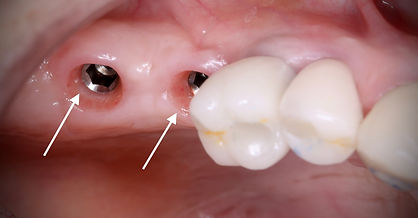

L'implant lui-même : il s'agit de la partie qui est insérée dans l'os de la mâchoire pour remplacer la racine de la dent manquante. L'implant est généralement en titane, un matériau bio-compatible qui est bien toléré par l'organisme. L'implant peut avoir différentes formes, longueurs et diamètres pour s'adapter à différents cas cliniques.

L'élément de connexion : c'est la partie qui relie l'implant à la prothèse dentaire (couronne, bridge, prothèse amovible) qui sera fixée sur l'implant. Cette pièce intermédiaire est souvent appelée "abutment" ou pilier implantaire . L'élément de connexion est généralement fabriqué en titane, en zircone ou en céramique.

La prothèse dentaire : c'est la partie visible de l'implant, qui remplace la dent manquante. La prothèse dentaire peut être fixée sur l'implant ou être amovible. La couronne dentaire ou le bridge peuvent être fabriqués à partir de différents matériaux, tels que la céramique, la porcelaine, le métal ou une combinaison de ces matériaux.